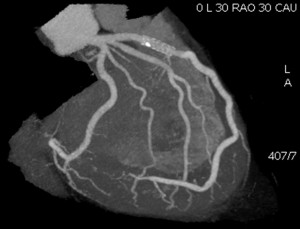

図1. Angiographic view

侵襲的冠動脈血管造影の撮影角度と同じ、冠動脈CT画像の表現方法.心臓CT黎明期に、循環器内科医にとっても、冠動脈CTの理解が容易となり、世界的に広まった表示方法である.